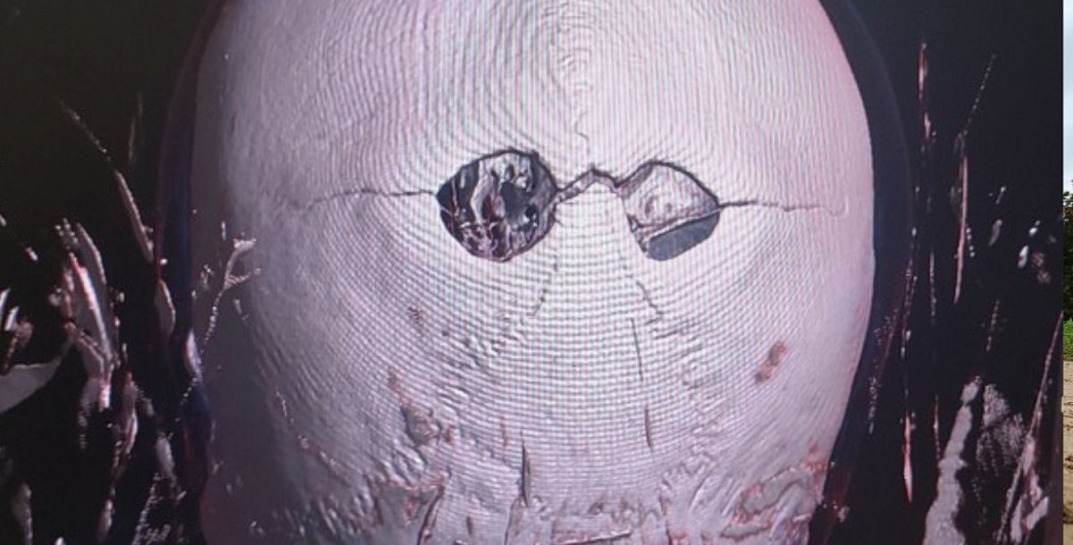

Первично, повреждение черепа, выявленное с помощью компьютерной томографии рентгенологами, было интерпретировано, как «дырчатый» перелом. Имевшийся перелом имел признаки, указывающие на действие тупого предмета с преобладающей контактирующей поверхностью, что могло послужить поводом к возбуждению уголовного дела.

При тщательном совместном с рентгенологами изучении мультиспиральной компьютерной томографии посредством графического представления отдельных анатомических структур в виде виртуальных трехмерных объектов, с помощью техники объемной (3D) визуализации выявлена аномалия развития костей свода черепа: теменные отверстия – парные округлые дефекты в задних парасагиттальных отделах теменных костей. Согласно литературным источникам, эти дефекты вовлекают как внутреннюю, так и наружную костные пластинки, что и наблюдалось в данном случае. Эти отверстия формируются в результате аномалии интрамембранозной оссификации в теменных костях, поэтому размеры могут быть различные. Прилегающие мягкие ткани головы всегда нормальные.